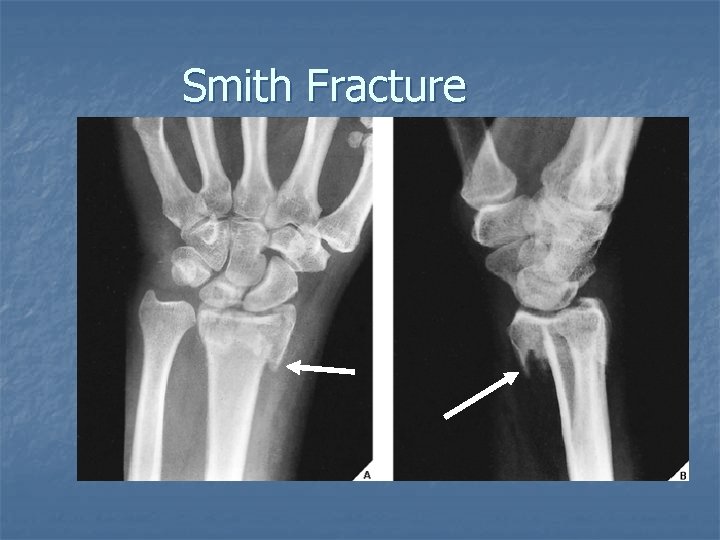

Smith Fracture n n n Fracture of the distal radius with volar displacement and angulation of the distal fragment Results from a fall on the back of the hand or a direct blow to the dorsum of the hand. Often referred to as a reverse Colles fracture.

Smith Fracture